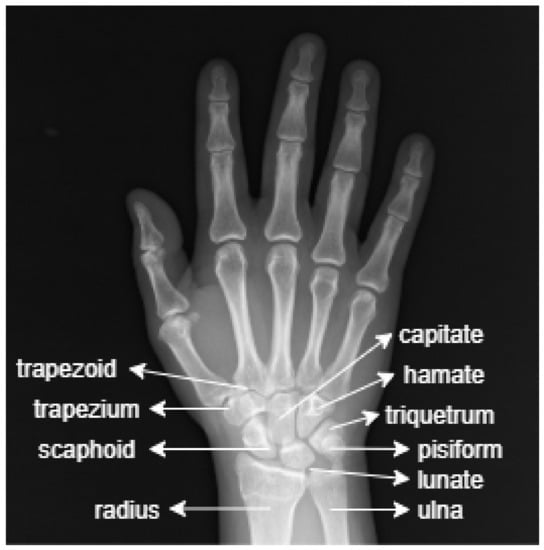

The anatomy of the wrist consists of radius, ulna and carpal bones. The carpal bones connect the hand to the forearm. Figure 1 shows a sample image of the anatomy of the wrist.

Figure 1.

The anatomy of the wrist.

The image in Figure 1 shows that the wrist is made up of eight small carpal bones in total. These are: scaphoid, lunate, trapezium, trapezoid, capitate, hamate, triquetrum and pisiform.

- Scaphoid: A long, boat-shaped bone under the thumb.

- Lunate: A crescent-shaped bone beside the scaphoid.

- Trapezium: A rounded, square-shaped bone above the scaphoid and under the thumb.

- Trapezoid: The bone beside the trapezium shaped like a wedge.

- Capitate: An oval bone in the middle of the wrist.

- Hamate: The bone under the pinky finger side of the hand.

- Triquetrum: The pyramid-shaped bone under the hamate.

- Pisiform: A small, round bone that sits on top of the triquetrum.

Under these carpal bones are located the radius and ulna bones [2]. The fractures in the wrist X-ray images used in this study are focused on the radius and ulna bones.